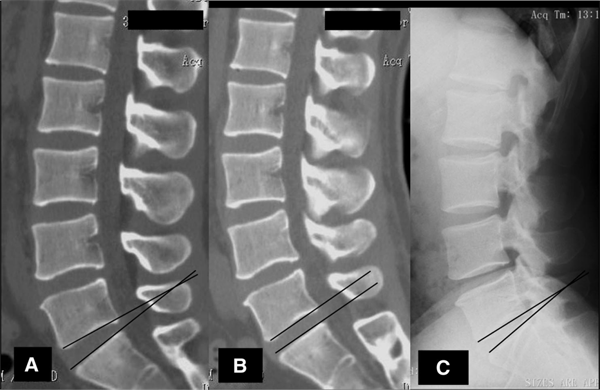

(A腰椎仰卧位、B仰卧位轴向加载、C站立位测量对比)[1]

如图所示,对照腰椎仰卧位,腰椎长度:轴向加载 -1.6%、站立位 -2.2%。L2/3和L3/4的节段前凸角:轴向加载、站立位都显著增加。

L5/S的节段前凸角、骨盆角度:轴向加载显著减小,站立位无显著变化。通过以上描述可以看出,CT/MR检查无法观察到患者在自然承重状态下关节的状态,对于站立位患者自然负重情况下发生的椎体变化、关节间隙变窄、椎间孔变窄等问题,CT和MR可能难以准确定位病灶。